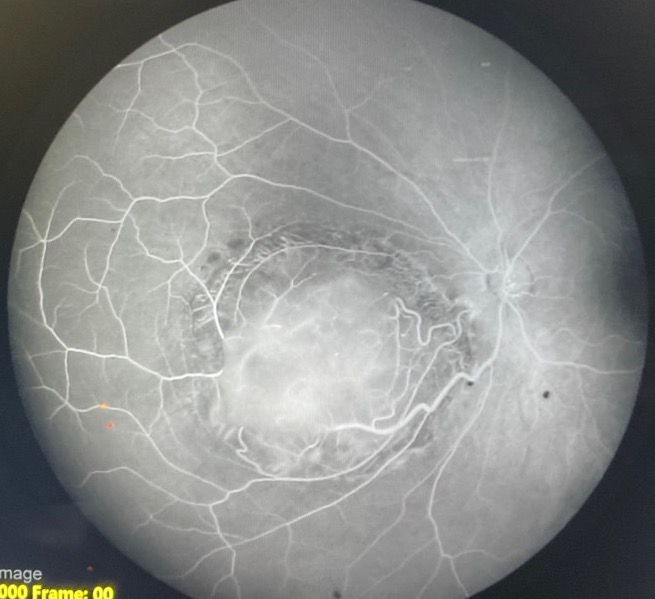

Fluorescein angiography of retinocytoma in the late phase. Retinal feeder vessels are mildly tortuous and of normal caliber. There is surrounding window defect from RPE atrophy and no intralesional vessels, leakage, or staining.